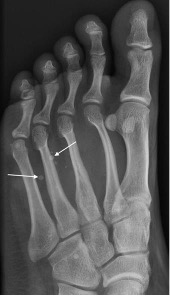

Sero-negative spondyloarthropathy

- Includes ankylosing spondylitis, psoriasis and Reiter’s syndrome; linked to HLA B27 antigen complexes

- Usually involves interphalangeal joints in an asymmetrical distribution

- Soft tissue swelling leads to dactylitis or ‘sausage digits’

- Loss of joint space and ill-defined erosions with proliferative new bone formation and periostitis

- Erosion of bone end into a sharpened pencil shape giving a ‘pencil in cup’ deformity

- Severe forms progress to ankylosis

- Fluffy new bone formation and erosions may occur at the calcaneal insertions of the Achilles and plantar fascia

Psoriatic arthropathy with new bone proliferation (arrowhead) and ‘pencil in cup’ appearance (arrow)